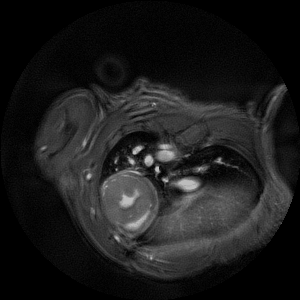

An extremely powerful instrument for most challenging murine imaging studies

The ultra-high field of the BioSpec 152/11 provides extreme sensitivity for greatest resolution. Its streamlined design for mice studies makes handling simple, while its powerful software guarantees best results. It can be equipped with the MRI CryoProbe to increase sensitivity even further and together with the gradient strength of up to 1000 mT/m, highest resolution is achieved. It is built with nitrogen-free Ultra Shielded and helium Refrigerated (US/R) magnet technology for long service intervals

• Crisp and highly resolved images with native gradient strength of 740 mT/m, upgradable to 1000 mT/m

• MRI CryoProbe for exceptional increase in sensitivity